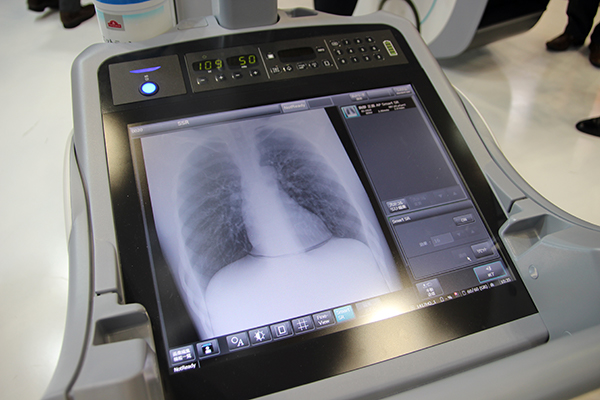

回診用X線撮影装置MobileDaRtの第8世代となる「MobileDaRt Evolution MX8 Version」は,新しく島津社製DR搭載タイプが発売となり実機が展示された。MX8 Versionは,「MX7」からデザインを一新。本体をコンパクト化し,X線管球の支柱に伸縮機構を備えたことで走行時に前方を確認しやすくなった。また,19インチのフルフラットモニタの搭載や,ワイヤレス曝射スイッチのオプション提供など,撮影業務を支援し,操作者の負担を軽減する豊富な機能を備えている。島津社製DRには,新しい画像強調処理オプション“Fine-View”など独自のテクノロジーが搭載される。

コンパクト化した「MobileDaRt Evolution MX8 Version」

島津社製DRを新しく搭載したMX8 Version